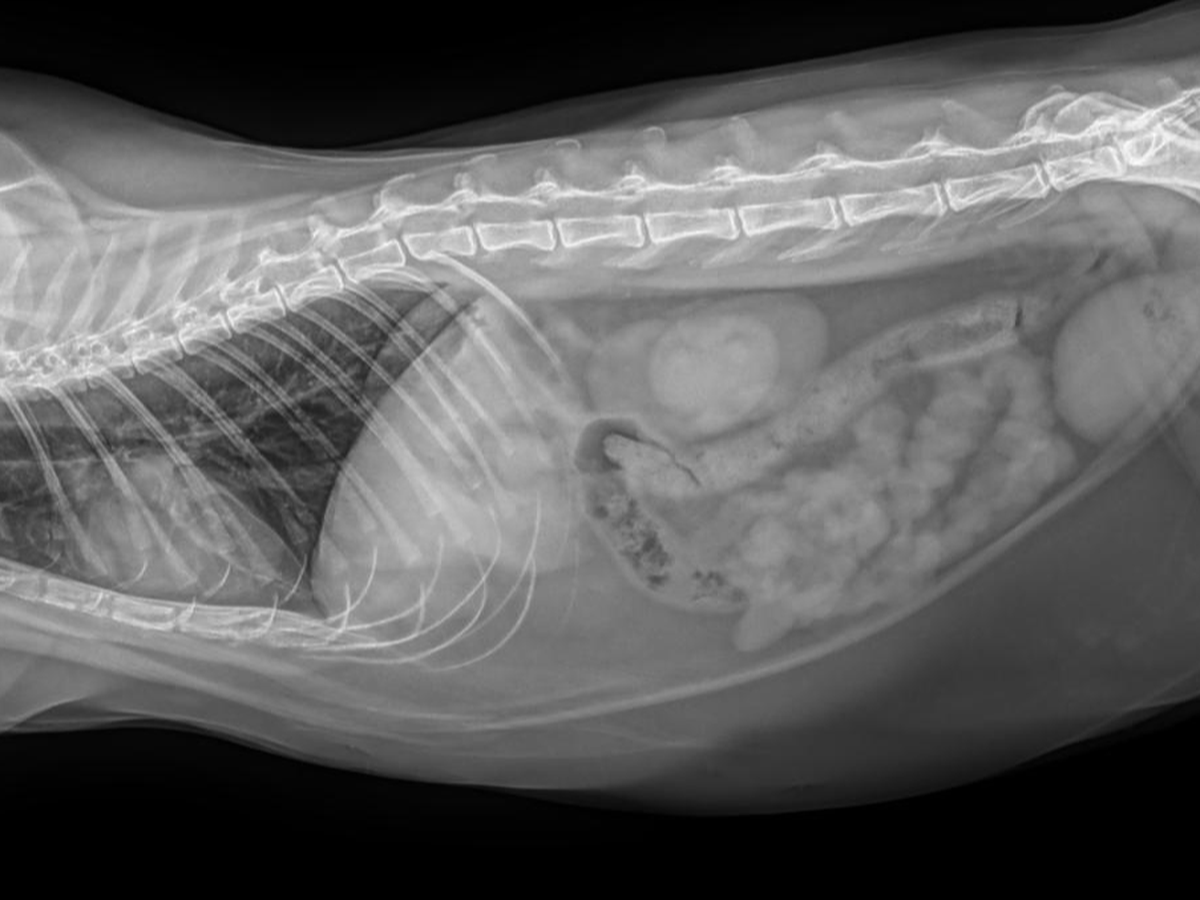

Maureen here. If you're on my Facebook, you've seen the saga of my cat Chichi swallowing a lot of polyester thread and needing surgery to untie his intestines or he probably would have died. March 26 is 3 weeks post surgery and he's almost eating normally, finally!